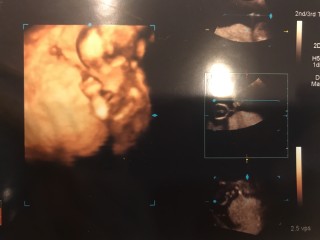

今日の検診から4Dエコーでした?今回は完全にずっと後ろ向いてて、性別はまだわかりませんでした。今の時期は検診が4週空くので、間の期間は不安もありますが、毎回検診で会えるのが楽しみです?手や足、耳もはっきり見えてクネクネと動いてて可愛かったです。私はつわりもほとんどなく、今も特に変わった違和感もないので、早く胎動を感じたりしたいです☆

綺麗な形の頭に感動。 先生からも良いショットだから写真持ち帰る?と 言われ頂いた写真です(笑)まだ性別は分からない ですが次回の健診で分かるかもしれないとの事で 楽しみです。